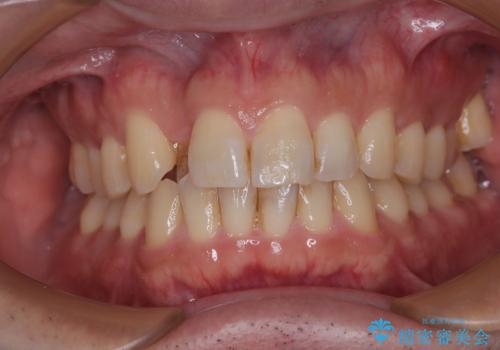

[ 矯正治療 ] 噛み合わせ前歯の見た目をきれいにしたい

![[ 矯正治療 ] 噛み合わせ前歯の見た目をきれいにしたいの症例 治療前](https://seimitsushinbi.jp/wp/wp-content/uploads/2025/08/IMG_7266-500x350.jpg?v=1754654745)